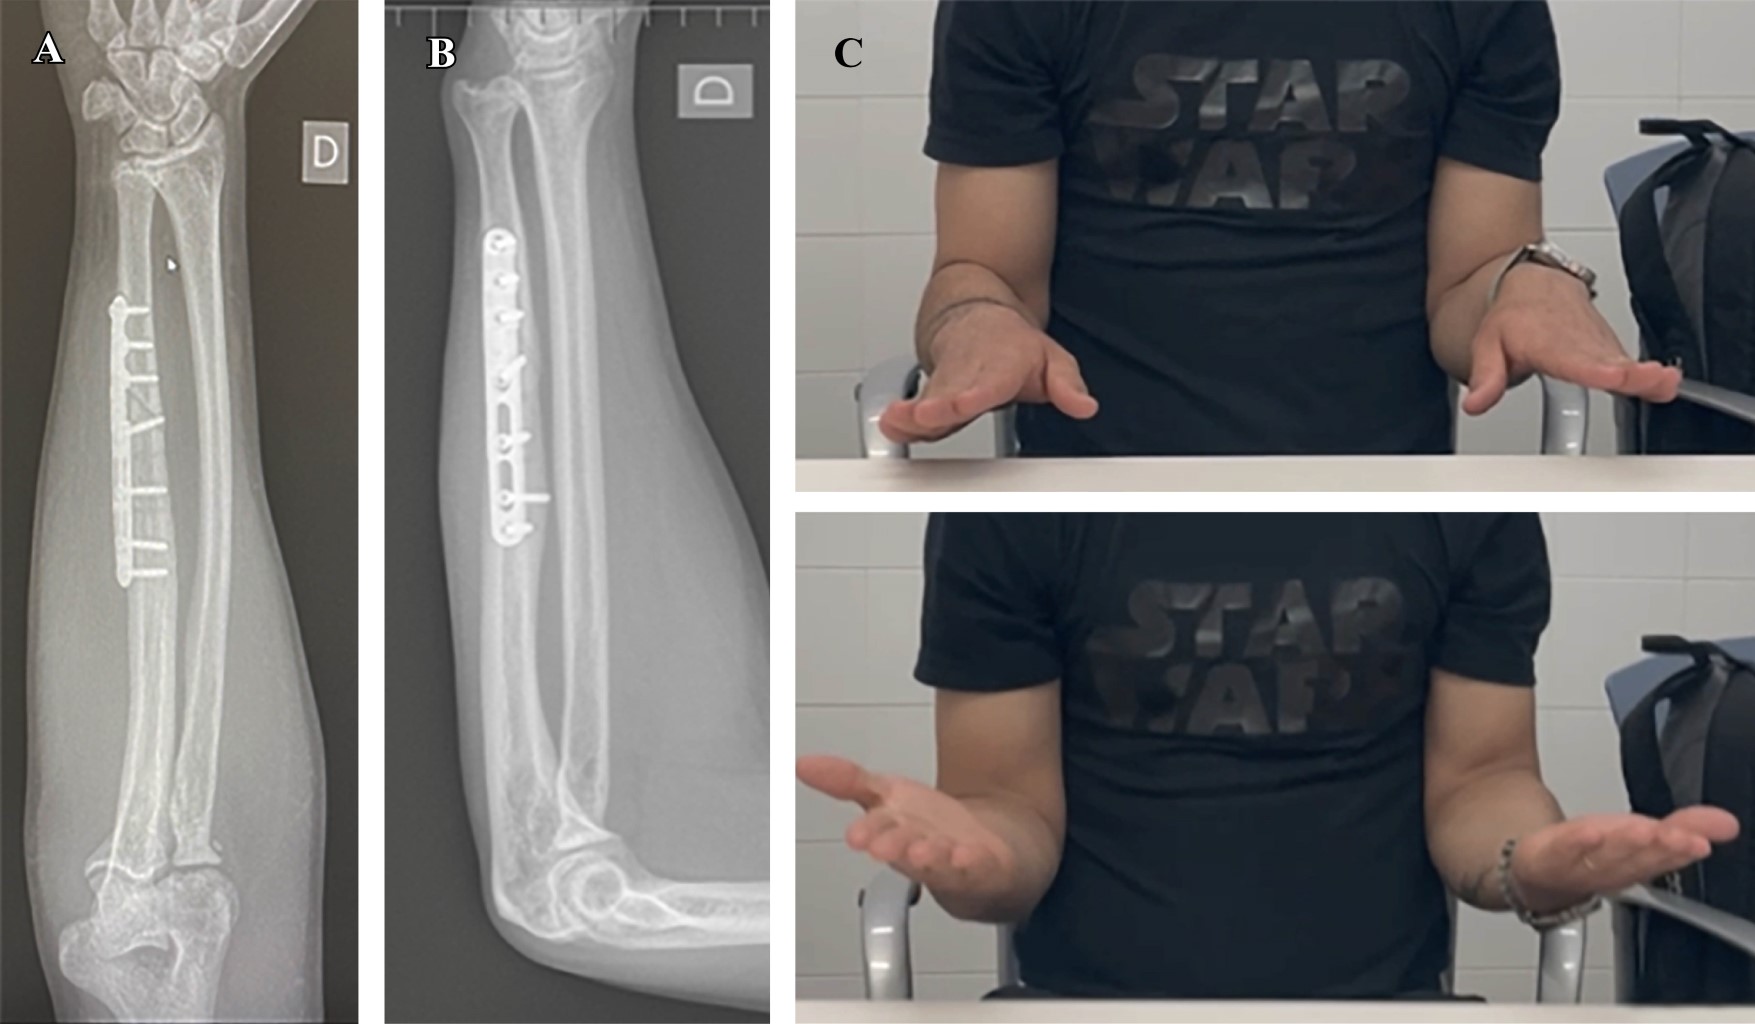

Introducción: el antebrazo puede considerarse como una articulación en sí misma donde interactúan el cúbito y el radio. Está constituida por la articulación radiocubital proximal (ARCP), la membrana interósea (MIO) con la banda medial como componente principal, y la articulación radiocubital distal (ARCD), que incluye el complejo fibrocartílago triangular (CFCT). La lesión de Essex-Lopresti (LEL) es una lesión compleja causada por una carga axial del antebrazo, que conlleva la disociación radiocubital longitudinal y la pérdida de estabilidad debido a la rotura de la MIO, la lesión de la ARCP con la cabeza del radio y lesión de la ARCD por afectación del CFCT. El diagnóstico precoz es crucial ya que el tratamiento de las lesiones crónicas plantea un importante desafío. Objetivo: describir la LEL crónica, revisar la literatura y compartir la experiencia de su tratamiento. Caso clínico: se describe el caso de un varón de 30 años que sufrió un accidente de moto en 2019. Diagnosticado inicialmente de fractura conminuta de cabeza radial derecha, fue tratado inicialmente mediante resección de la misma. El paciente visitó nuestro centro en 2023, la exploración clínica mostró dolor en muñeca y una protrusión dorsal de cúbito reductible pero inestable, sin dolor ni limitación de movimiento en el codo y antebrazo. Las pruebas complementarias, radiología simple y RMN, mostraron una varianza cubital positiva, una subluxación dorsal del cúbito a nivel de la muñeca y una lesión del CFCT, sin evidencia de ruptura aguda de la MIO. Se llevó a cabo un examen bajo anestesia y una evaluación fluoroscópica para examinar la estabilidad y el rango de movimiento del codo y la ARCD, así como la estabilidad longitudinal del antebrazo mediante tracción. Al no observarse inestabilidad longitudinal, se realizó una osteotomía de acortamiento del cúbito de 10 mm y se fijó con una placa y tornillos. De forma artroscópica, se observó la desinserción del CFCT y se reinsertó mediante una modificación de la técnica de Mantovani. Se inmovilizó con una férula de Münster. A los seis meses de seguimiento, tiene un EVA de 0 en codo y muñeca, y una flexión dorso/volar de 80º/80º, y un déficit de supinación/pronación de 10o/10o. Conclusiones: la LEL es una patología infrecuente pero desafiante para el cirujano. Las opciones terapéuticas incluyen diversas intervenciones quirúrgicas, siendo el acortamiento del cúbito con reparación del CFCT una opción viable en casos crónicos sin inestabilidad longitudinal.

Figura 1